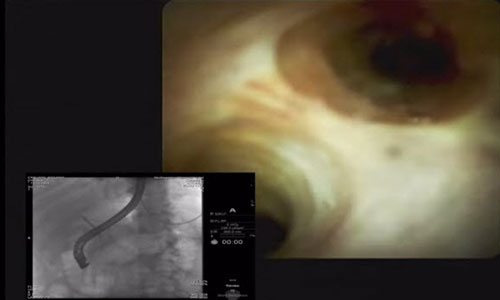

SpyGlass™ DS

Sistema de visualización directa

El sistema de visualización directa SpyGlass™ DS en acción

El Dr. Sri Komanduri desarrolló este caso con el sistema SpyGlass DS y lo publicó en YouTube. También aportó los siguientes comentarios sobre el sistema: "mejoró significativamente la facilidad de uso y las ópticas son fantásticas. Este caso destaca la manera en la que la colangioscopía digital puede cambiar los resultados de los pacientes significativamente".

Extracción de cálculos

El Dr. Gumustop utiliza el sistema SpyGlass DS para extraer un cálculo de impacto grande en el conducto colédoco distal.

"El procedimiento duró menos de 1 hora y el dolor del paciente se resolvió de inmediato. Después de haberse sometido a 4 CPER anteriores, el paciente se sintió muy aliviado de que logré extraer el cálculo y evitarle una cirugía".

Bora Gumustop, MD

Albany, Nueva York